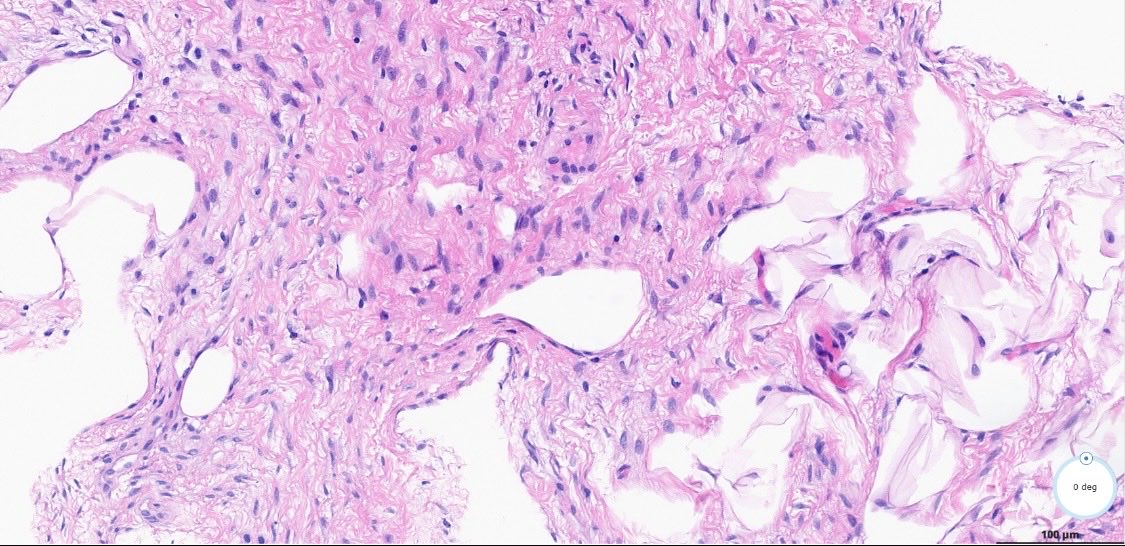

#DrBuiBSTCaseCollection 🌻Fat-rich Desmoid Fibromatosis. This case is CTNNB1-mutated, CD34 IHC-negative. A rare finding in a relatively common soft tissue tumor. Not a spindle cell lipoma. @PathX @Pathtwitter@USFpathology⁩ ⁦@MoffittNews⁩ ⁦@CAPA_comm

DrBuiPathology's tweet image. #DrBuiBSTCaseCollection 🌻Fat-rich Desmoid Fibromatosis. This case is CTNNB1-mutated, CD34 IHC-negative. A rare finding in a relatively common soft tissue tumor. Not a spindle cell lipoma. @PathX @Pathtwitter ⁦@USFpathology⁩ ⁦@MoffittNews⁩ ⁦@CAPA_comm⁩